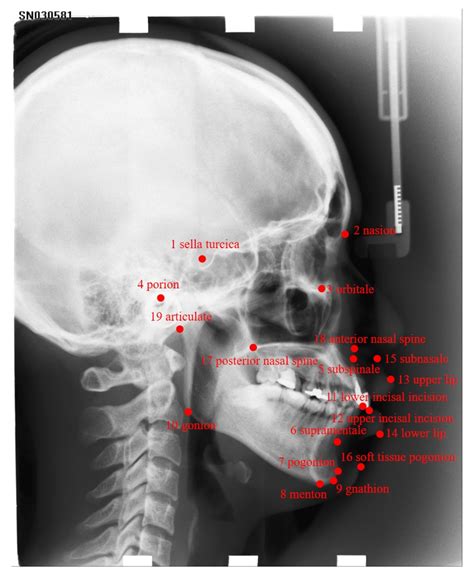

Interpreting a Cephalometric X Ray requires a thorough understanding of craniofacial anatomy and orthodontic principles. The orthodontist analyzes various landmarks and measurements to assess the patient’s dental and skeletal relationships. Some of the key landmarks and measurements include:

Key Landmarks

The following table outlines some of the key landmarks used in Cephalometric X Ray analysis:

Landmark Description

Sella (S) The center of the sella turcica, a depression in the sphenoid bone

Nasion (N) The most anterior point of the frontal bone at the nasofrontal suture

Orbitale (Or) The lowest point on the inferior margin of the orbit

Pogonion (Pog) The most anterior point on the chin

Gnathion (Gn) The most inferior point on the symphysis menti

Key Measurements

The following measurements are commonly used to assess dental and skeletal relationships:

• SNA angle: Measures the relationship between the maxilla and the cranial base

• SNB angle: Measures the relationship between the mandible and the cranial base

• ANB angle: Measures the relationship between the maxilla and the mandible

• Wits appraisal: Measures the anteroposterior relationship of the maxilla and mandible

• Gonial angle: Measures the angle of the mandible